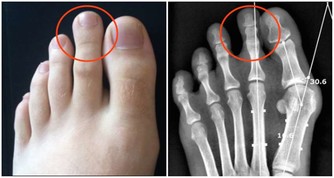

3、疝

腹股溝疝,腹壁切口疝和臍疝。